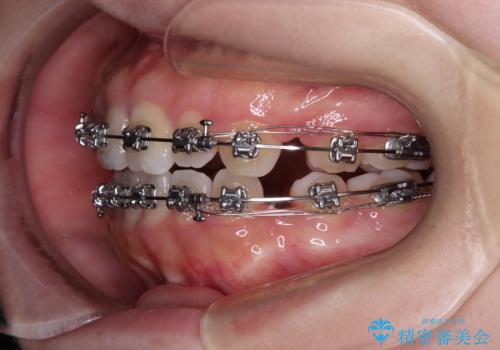

- メタルブラケット

- 1年9ヶ月

舌の突出癖により上下前歯は接触できず、更には前方に押し出されて出っ歯になっている状態でした。

上下左右の第一小臼歯4本を抜歯し、ワイヤー装置での抜歯矯正を行っていくのですが、原因である舌の突出癖を改善しないことには治療がうまく進められないため、舌のトレーニングを徹底するよう指導していくこととしました。

当初は舌のトレーニングをしっかりと行ってくださったおかげで、短い期間で治療を終えることができました。